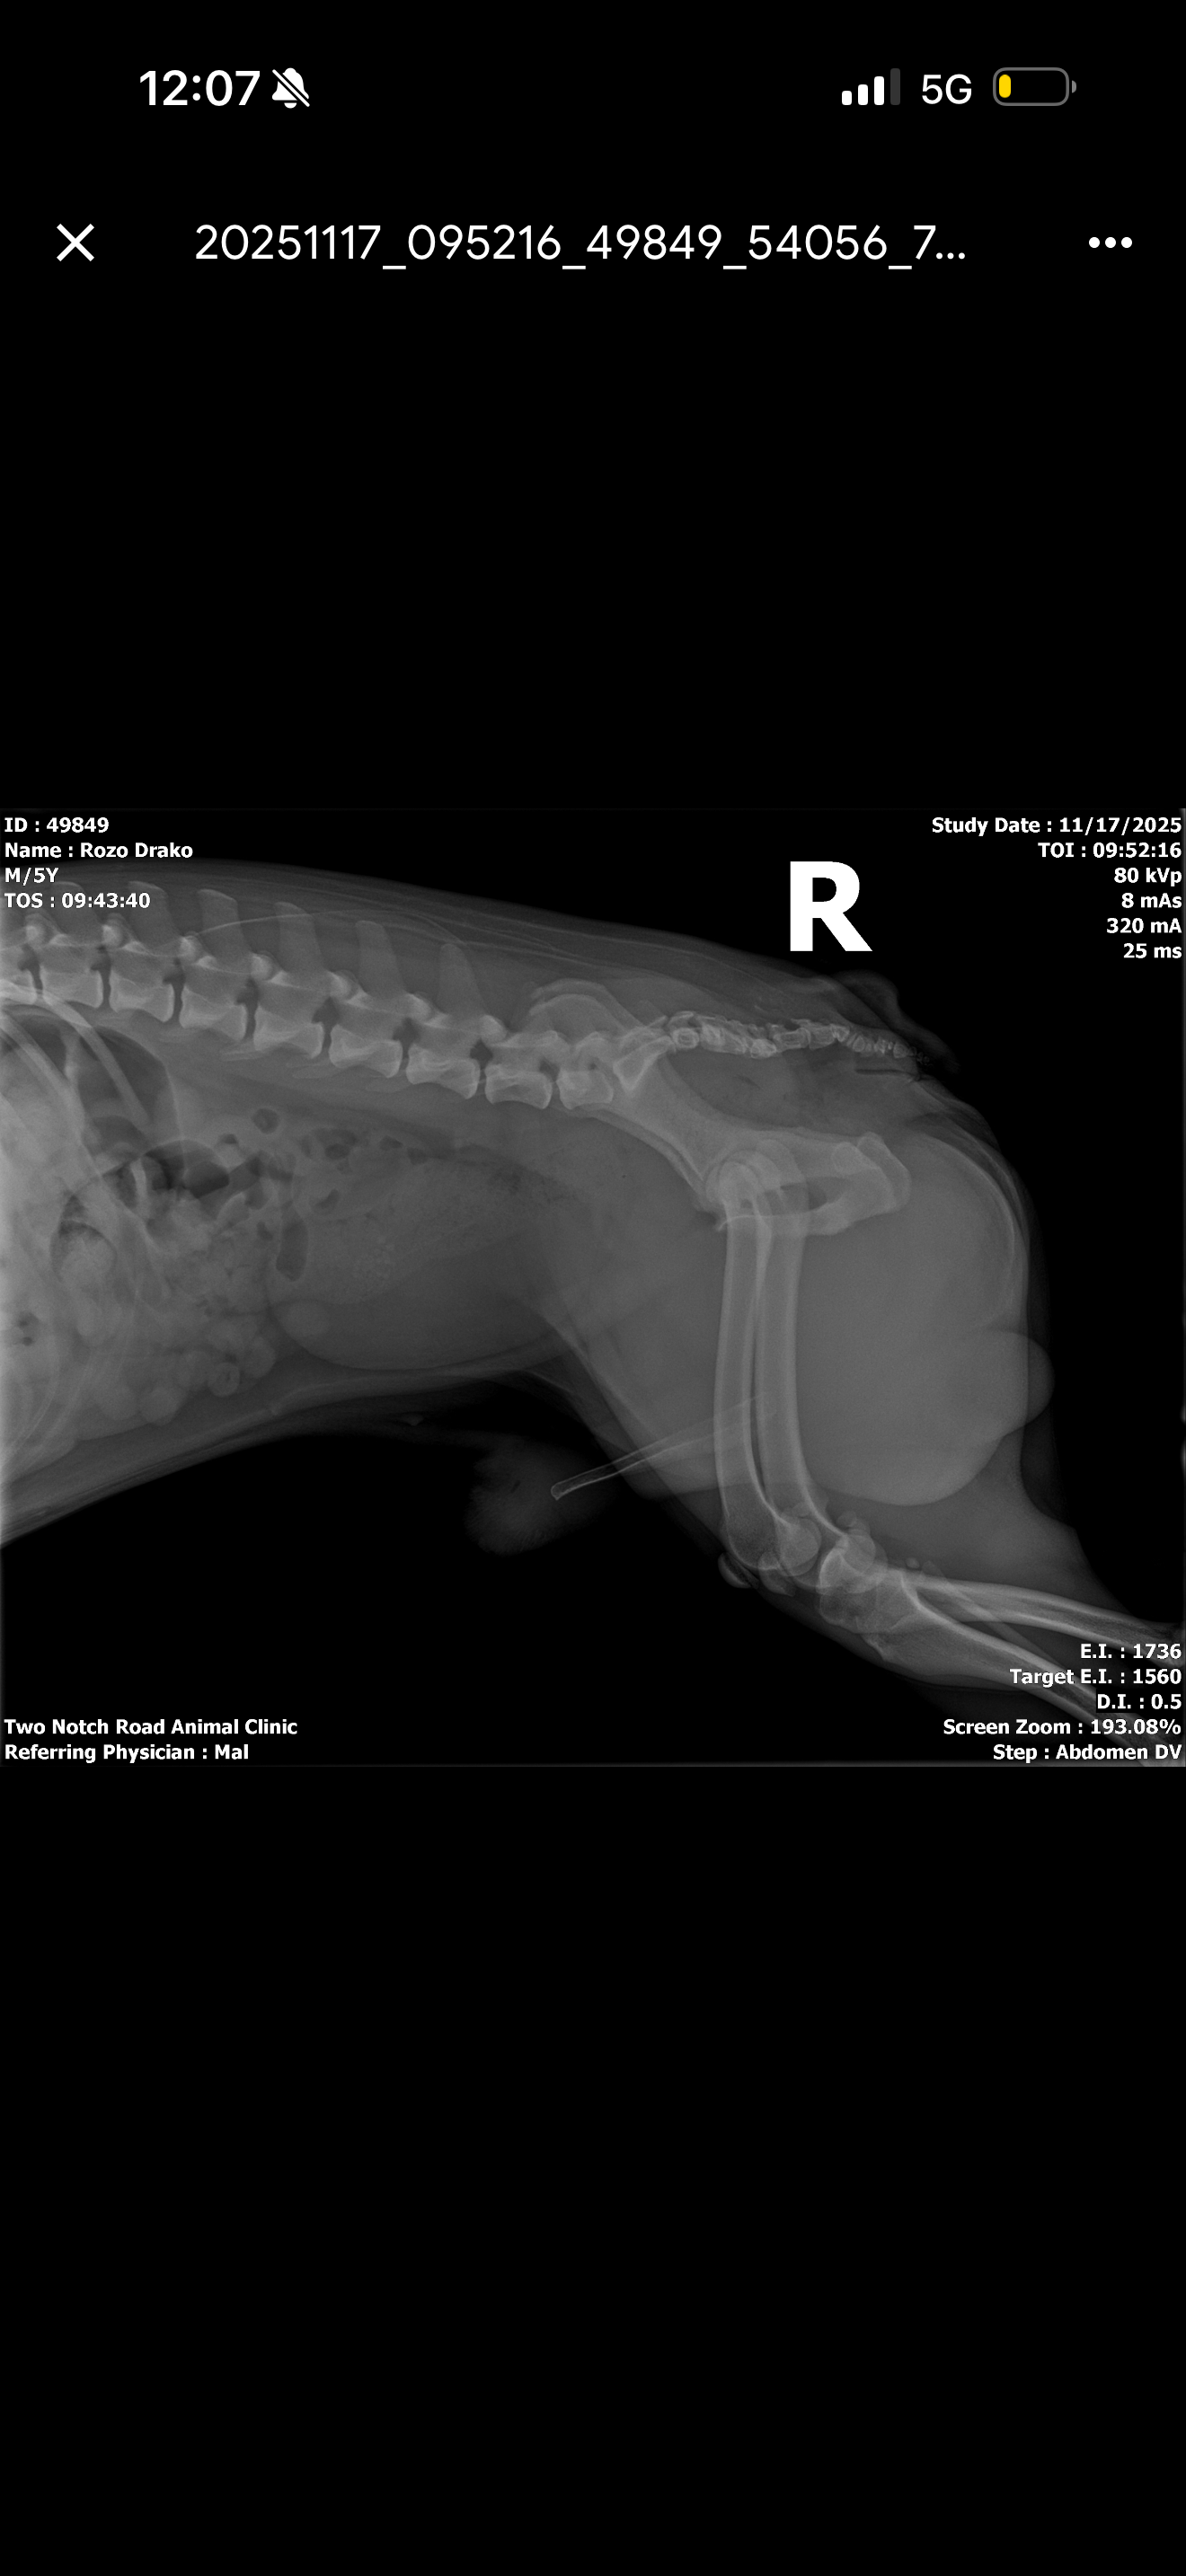

Su estado ha cambiado por completo y se nota que está sufriendo. El veterinario confirmó que tiene cálculos que bloquean su vejiga y que necesita cirugía lo antes posible para evitar complicaciones graves.

His condition has changed completely, and it’s obvious he is suffering. The vet confirmed he has bladder stones blocking his urinary system and needs surgery as soon as possible to prevent severe complications.